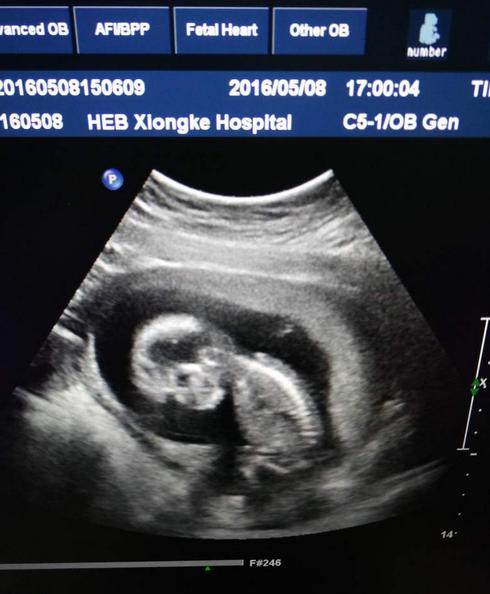

产检时做出的成像是四维图像,本身就比较难以判断胎儿的性别,一般都是根据医生们的经验来推断的,所以存在判断错误也是很正常的情况。宝宝们在妈妈肚子里的姿势不同,也可能会造成一些遮挡与错位的情况,让最后产检得出的成像看起来像是某种性别,其实并不符合宝宝的真实性别。